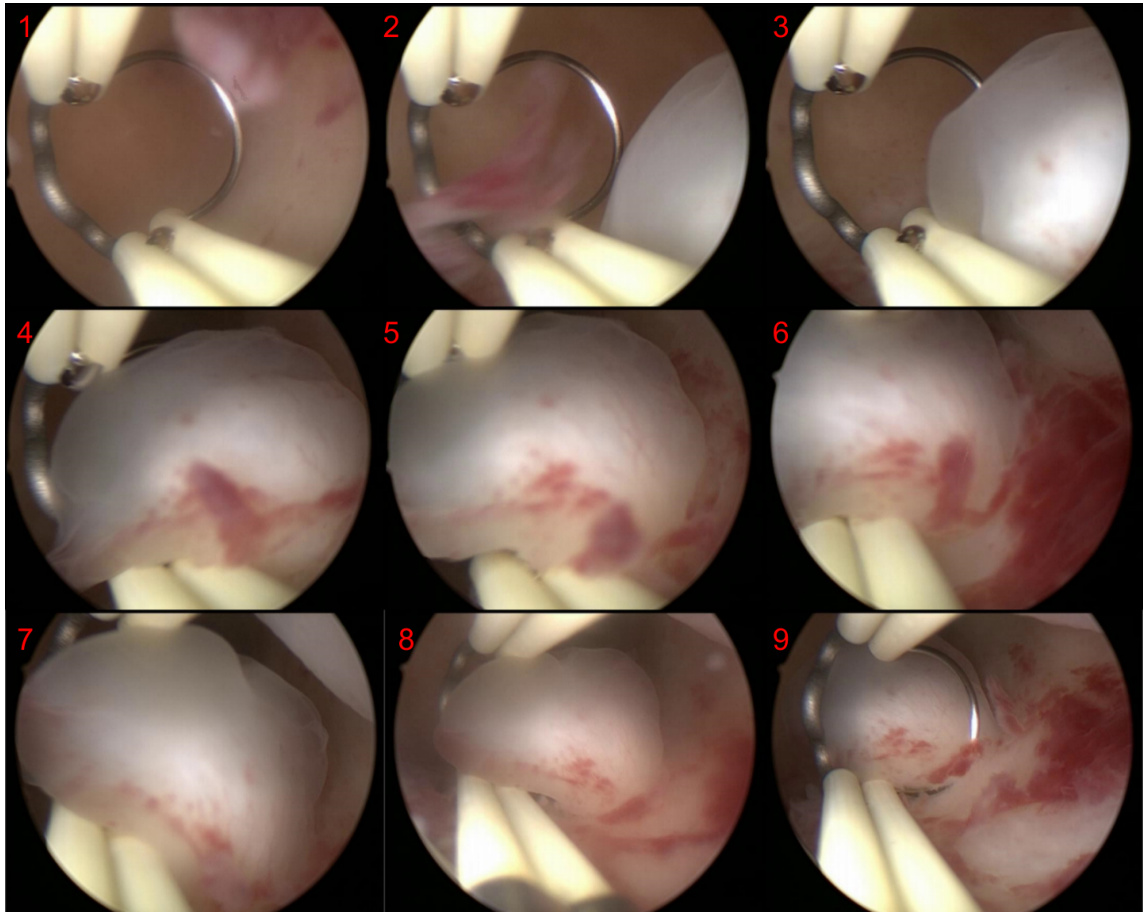

6.2.2 Case 2: Endoscopic series operation analysis

CASE 2

CASE 2 Control Group

Prompt: This is a sequence of pictures from an endoscopic surgery. Please analyze each step of the sequence.

提示:这是一组内窥镜手术的连续图像。请分析该序列中的每个步骤。

GPT-4V Response:

CASE 2 Providing the tasks

案例 2: 任务分配

Prompt: This is a sequence of pictures showing the localization of polyps during a hy ster osco pic polyp ec to my procedure. Please analyze each step of the sequence.

提示:这是一组展示宫腔镜息肉切除术中息肉定位过程的图片序列。请分析该序列的每个步骤。

GPT-4V 响应: